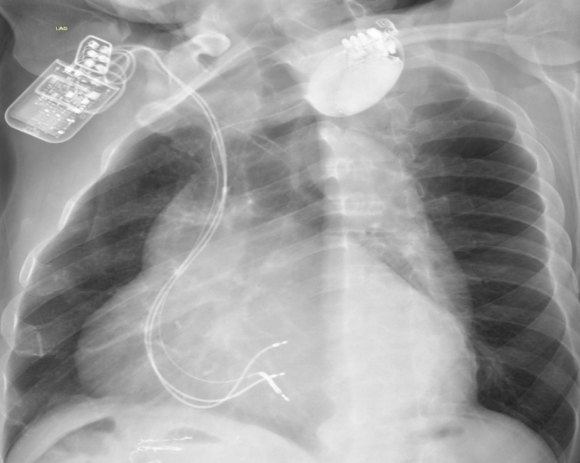

CCM+ICD术后X片——正位及左前斜位

3、CCM联合ICD一站式手术的难点:精准的放置三根导线对此次手术尤为关键,也是手术的难点,不仅要求导线参数满足要求,还需要兼顾三根导线放置的位置和间距。首先是准备静脉通路,在右侧锁骨下静脉穿刺,送入导丝,在透视下确认钢丝成功进入右心系统;之后进行囊袋制作;随后进行起搏导线植入,两根起搏导线之间的距离在2cm以上,ICD导线与普通导线距离3cm以上(ICD导线除颤线圈长度,可作为导线之间距离的参考),从而保证CCM的正常感知与发送且不会互相干扰,最终所有电极导线都被精准完成植入,分别测试三根电极导线的起搏阈值和起搏阻抗并记录。连接导线与脉冲发生器,设定输出为7.5V。联合测试,三根电极均可以正常工作且彼此无干扰。同时考虑到除颤的效果,将ICD放置在左侧,CCM放置在右侧。此患者术后心电图对比,完美展示了自身心律与起搏心率下CCM正常工作。